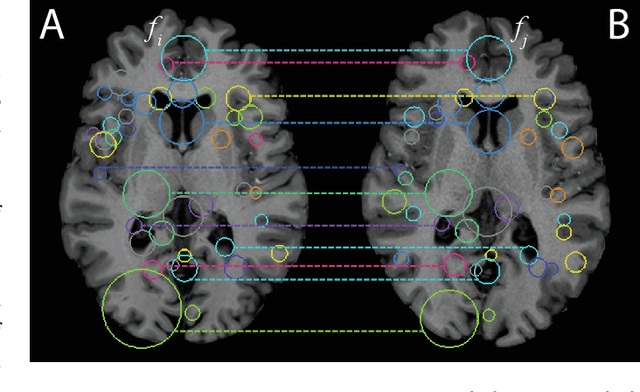

Abstract:This paper proposes to extend local image features in 3D to include invariance to discrete symmetry including inversion of spatial axes and image contrast. A binary feature sign $s \in \{-1,+1\}$ is defined as the sign of the Laplacian operator $\nabla^2$, and used to obtain a descriptor that is invariant to image sign inversion $s \rightarrow -s$ and 3D parity transforms $(x,y,z)\rightarrow(-x,-y,-z)$, i.e. SP-invariant or SP-symmetric. SP-symmetry applies to arbitrary scalar image fields $I: R^3 \rightarrow R^1$ mapping 3D coordinates $(x,y,z) \in R^3$ to scalar intensity $I(x,y,z) \in R^1$, generalizing the well-known charge conjugation and parity symmetry (CP-symmetry) applying to elementary charged particles. Feature orientation is modeled as a set of discrete states corresponding to potential axis reflections, independently of image contrast inversion. Two primary axis vectors are derived from image observations and potentially subject to reflection, and a third axis is an axial vector defined by the right-hand rule. Augmenting local feature properties with sign in addition to standard (location, scale, orientation) geometry leads to descriptors that are invariant to coordinate reflections and intensity contrast inversion. Feature properties are factored in to probabilistic point-based registration as symmetric kernels, based on a model of binary feature correspondence. Experiments using the well-known coherent point drift (CPD) algorithm demonstrate that SIFT-CPD kernels achieve the most accurate and rapid registration of the human brain and CT chest, including multiple MRI modalities of differing intensity contrast, and abnormal local variations such as tumors or occlusions. SIFT-CPD image registration is invariant to global scaling, rotation and translation and image intensity inversions of the input data.

Abstract:We propose a novel pairwise distance measure between variable-sized sets of image keypoints for the purpose of large-scale medical image indexing. Our measure generalizes the Jaccard index to account for soft set equivalence (SSE) between set elements, via an adaptive kernel framework accounting for uncertainty in keypoint appearance and geometry. Novel kernels are proposed to quantify the variability of keypoint geometry in location and scale. Our distance measure may be estimated between $N^2$ image pairs in $O(N~\log~N)$ operations via keypoint indexing. Experiments validate our method in predicting 509,545 pairwise relationships from T1-weighted MRI brain volumes of monozygotic and dizygotic twins, siblings and half-siblings sharing 100%-25% of their polymorphic genes. Soft set equivalence and keypoint geometry kernels outperform standard hard set equivalence (HSE) in predicting family relationships. High accuracy is achieved, with monozygotic twin identification near 100% and several cases of unknown family labels, due to errors in the genotyping process, are correctly paired with family members. Software is provided for efficient fine-grained curation of large, generic image datasets.